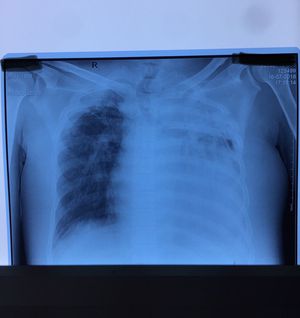

Can someone tell what the DX is?

Old man came with a chest pain and here the thorax Ro

Atelectasis?????..........__As well as the trachea are rounded by J shape ....It was lung volume are loss and the right upper lobe (apex) are always infected........

Collapsed lung (atelectasis) cud be due to accumulation of air, blood, inflammatory tissues